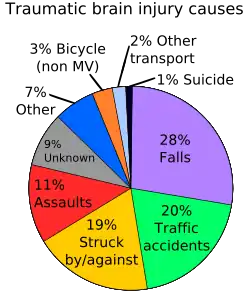

Traumatic brain injury happens when the head suffers from a sharp blow, or suddenly accelerates or decelerates. In these cases, the brain gets churned around, and can be damaged by the bony bumps and knobs inside the skull, or by the twisting and tearing of fibres in the brain.[1] If the traumatic brain injury is severe enough, it can lead to an initial coma, which is then followed by a time of post-traumatic amnesia. Post traumatic amnesia typically resolves itself gradually, however it will leave a mild, but permanent deficit in the patient's memory.[1]